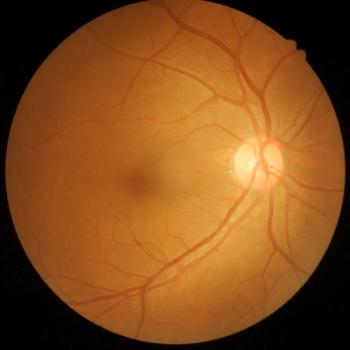

A retrospective study indicated the safety and efficacy of FA implants, exhibiting its success in lowering central retina thickness.

Recent results have confirmed faricimab’s efficacy, although a small sample size and short follow-up period invite further studies.

Type 2 macular neovascularization, reductions in outer nuclear layer and central foveal thickness, and intraretinal fluid may indicate higher odds of retinal atrophy.

Panretinal photocoagulation and anti-VEGF therapy combined also results in better BCVA and were less likely to require additional treatment within 1 year.